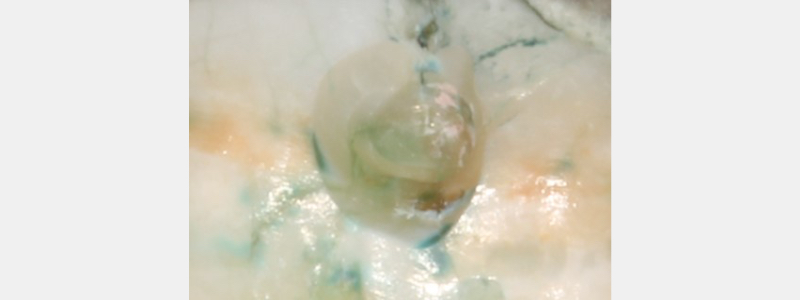

Although caries-indicating dyes are not highly specific, the intensity of the stain can be utilized to remove stained areas selectively. In general, areas with a darker, more intense stain tend to have more demineralization and carious bacteria. Areas with a lighter stain may not be affected and can be left in place.

As a result, some protocols for the conservative treatment of deep carious lesions advise removing the darkly stained dentin while leaving the lightly stained dentin in place and ensuring a peripheral seal of healthy tooth structure when using a caries detection dye during caries excavation.

Although there are drawbacks to using caries detection dyes, they can be helpful when used judiciously. Dark, intensely stained areas can be removed confidently; however, lightly stained dentin areas do not need to be aggressively excavated.

Indiscriminately removing dentin stained by caries detection dyes will lead to over preparation and can increase the risk of an inadvertent pulpal exposure.